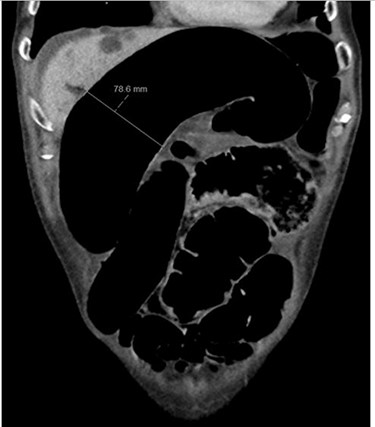

Blood tests on admission were unremarkable. Each admission, the patient’s plain abdominal films showed dilated large bowel loops consistent with sigmoid volvulus (Fig. 1). A subsequent computed tomography (CT) of the abdomen and pelvis with intravenous contrast revealed dilated large bowel and was reported as sigmoid volvulus with no evidence of perforation (Fig. 2). Caecal volvulus was not appreciated on this scan.

Case one: coronal slice of a CT scan of the abdomen and pelvis with intravenous contrast showing dilated large bowel.